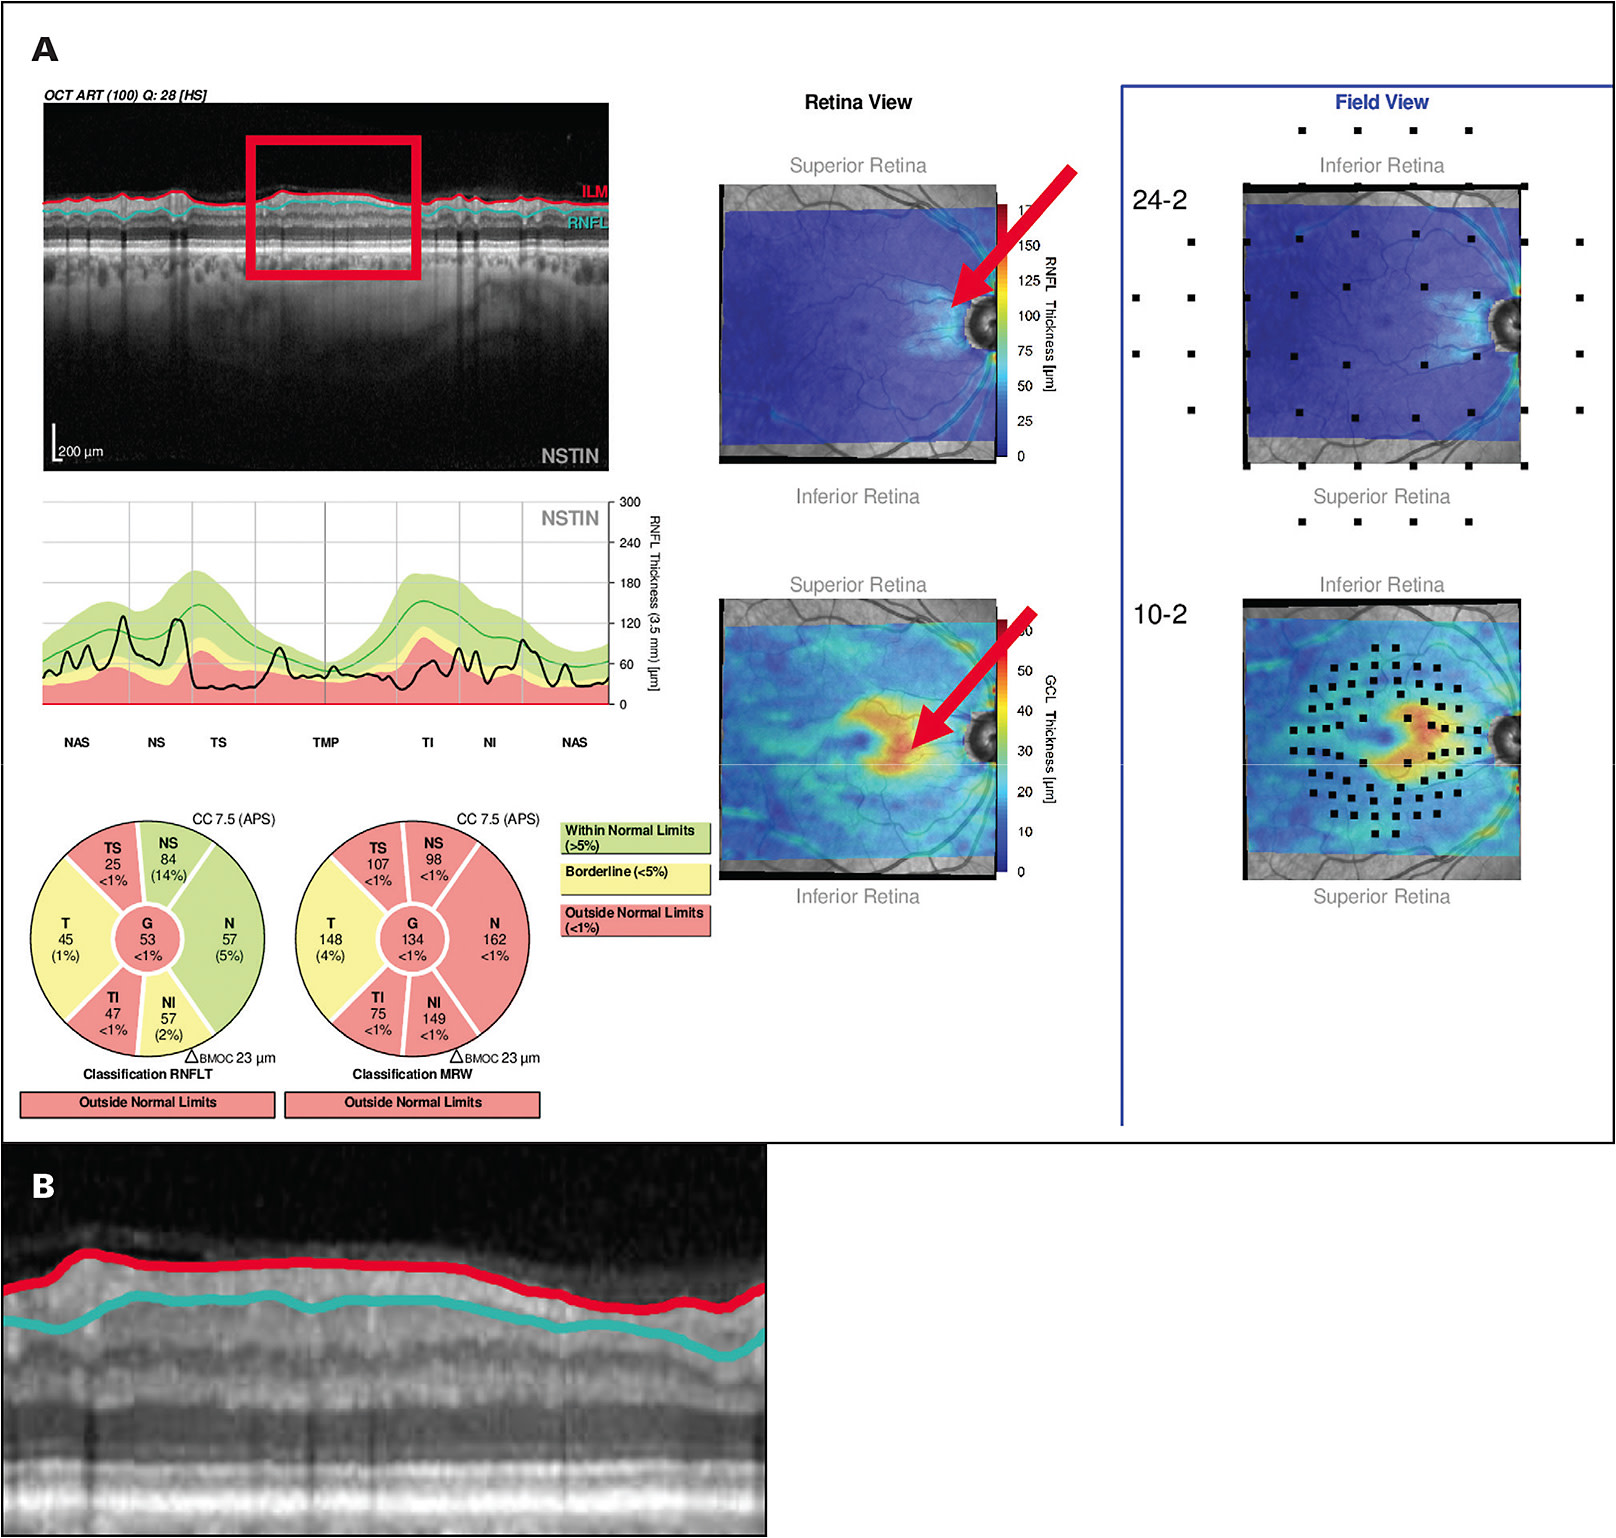

A: Yes. Many clinicians believe that if the average circumpapillary RNFL thickness, a common summary statistic, is less than about 50 µm to 60 µm, then OCT cannot be used to study or follow eyes with high myopia. While this is true for summary statistics, it is not true if you look at the B-scan image. Figure 2 shows an OCT report illustrating how preserved RNFL can be seen on OCT images in many eyes with advanced glaucoma. Our rule of thumb is that if you have any points remaining on your 10-2 visual field or your 24-2 visual field better than -8 dB, then some RNFL tissue is remaining, and you will be able to follow that remaining RNFL with an OCT.1,2,4

A: Several companies have incorporated the work we have done to allow the clinician to make a faster and more accurate diagnosis. Both Topcon and Heidelberg have “Hood Reports” that are based upon our work and incorporate the B-scan images and probability maps mentioned earlier. Figure 2A shows an example. These reports are based upon over 10 years of working with ophthalmologists.9-11 The reports also have 24-2 and 10-2 visual field locations superimposed to make it easy to compare the visual field to the OCT. Use of such reports will help the clinician avoid the dangers inherent in the myths we have been discussing. GP